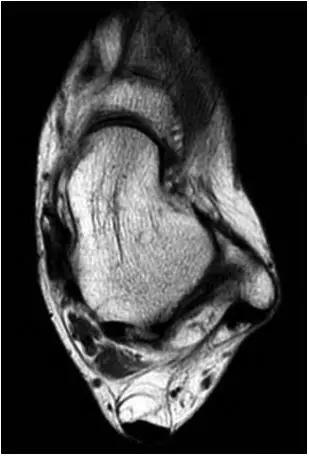

6.后踝撞击综合症:

- 骨性撞击多见,例如距骨后三角骨损伤,距骨或跟骨后突过度增生。软组织撞击表现为后胫腓韧带下部分、横韧带、后踝间韧带的撕裂或肥厚增生。

- 影像学表现为距骨后三角骨的存在或损伤以及距骨后突骨赘形成,导致踝关节跖屈受限,可伴随拇长屈肌肌腱鞘炎症及邻近滑膜不同程度的炎性增生 。

- MRI 检查示距后三角骨及周围软组织有水肿信号,距后三角骨和距骨之间正常的低信号纤维连接中断,出现液性信号。

3、MR表现:

- 三角籽骨或距骨后三角结构模糊和变形,T1WI信号降低, T2WI信号升高,

- 周围脂肪水肿,

- 踇趾长屈肌腱信号升高,见鞘膜积液,